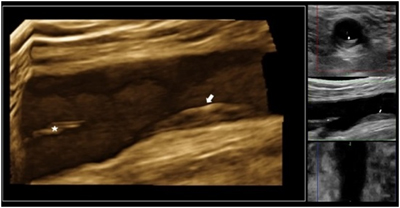

3D de la arteria femoral derecha donde se aprecia una evidente infiltración y protrusión de la pared del vaso hacia la luz que corresponde a una placa de aterosclerosis (flecha) antes de la bifurcación en sus ramas superficial y profunda (asterisco). Esta placa ocasiona una ligera obstrucción del tamaño de la luz vascular (entorno al 20%), es homogénea en su composición y no presenta datos de complicaciones como ulceras o trombos en su superficie.